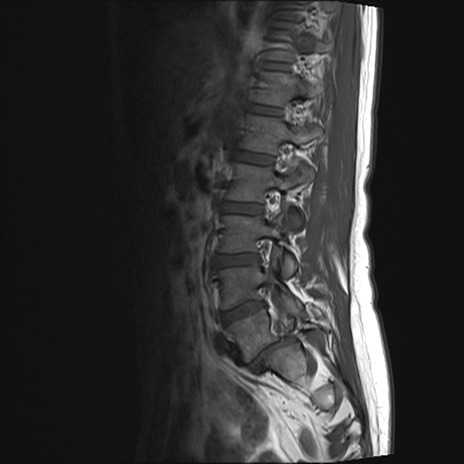

腰椎MRI

T2WI(横断像)

横断像と矢状断像